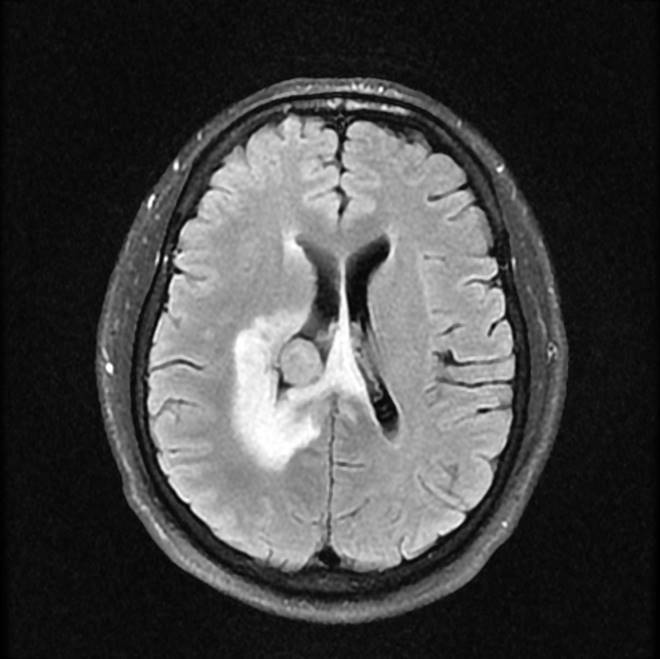

磁共振影像圖

圖1

MR診斷:右側(cè)側(cè)腦室三角區(qū)及側(cè)腦室旁占位,考慮惡性腫瘤可能,間變型腦膜瘤?轉(zhuǎn)移瘤?

MR鑒別診斷

常規(guī)MR檢查是診斷腦膜瘤的有效手段,可以明確腫瘤發(fā)生的部位、形態(tài)和數(shù)目等特征以及病變向鄰近腦實質(zhì)侵犯的程度和范圍,典型腦膜瘤呈等或(和)稍長T1、等或(和)稍長T2信號,??娠@示完整的包膜,增強掃描因腫瘤內(nèi)部新生血管通透性不同呈不同程度強化,由于腫瘤組織的強化程度與腫瘤的惡性程度不完全一致,導致MR常規(guī)檢查在腦膜瘤分級分型方面仍存在一定的困難。擴散加權成像( diffusion weighted imaging,DWI) 及表觀擴散系數(shù)( apparent diffusion coefficient,ADC) 被廣泛用于腦腫瘤的分級、分子分型和腫瘤侵襲性預測,并取得了良好的性能。目前,對于非典型腦膜瘤腦實質(zhì)侵犯的診斷的金標準依賴于組織病理學。